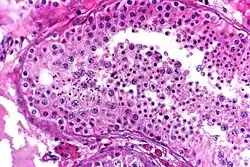

![]() Seminiferous tubule with maturing sperm. H&E stain. | |